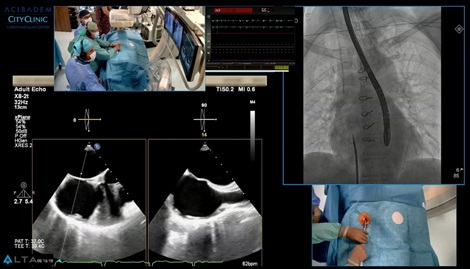

Live case: Имплантиране на TAVI при пациент с екстремно изкривяване на гръбначния стълб и абдоминалната аорта, с достъп през артерия на горен крайник

В настоящия Live case можете да проследите една нестандартна, изцяло ендуваскуларна операция, извършена от проф. Иво Петров, д.м.н. и доц. Зоран Станков, д.м.